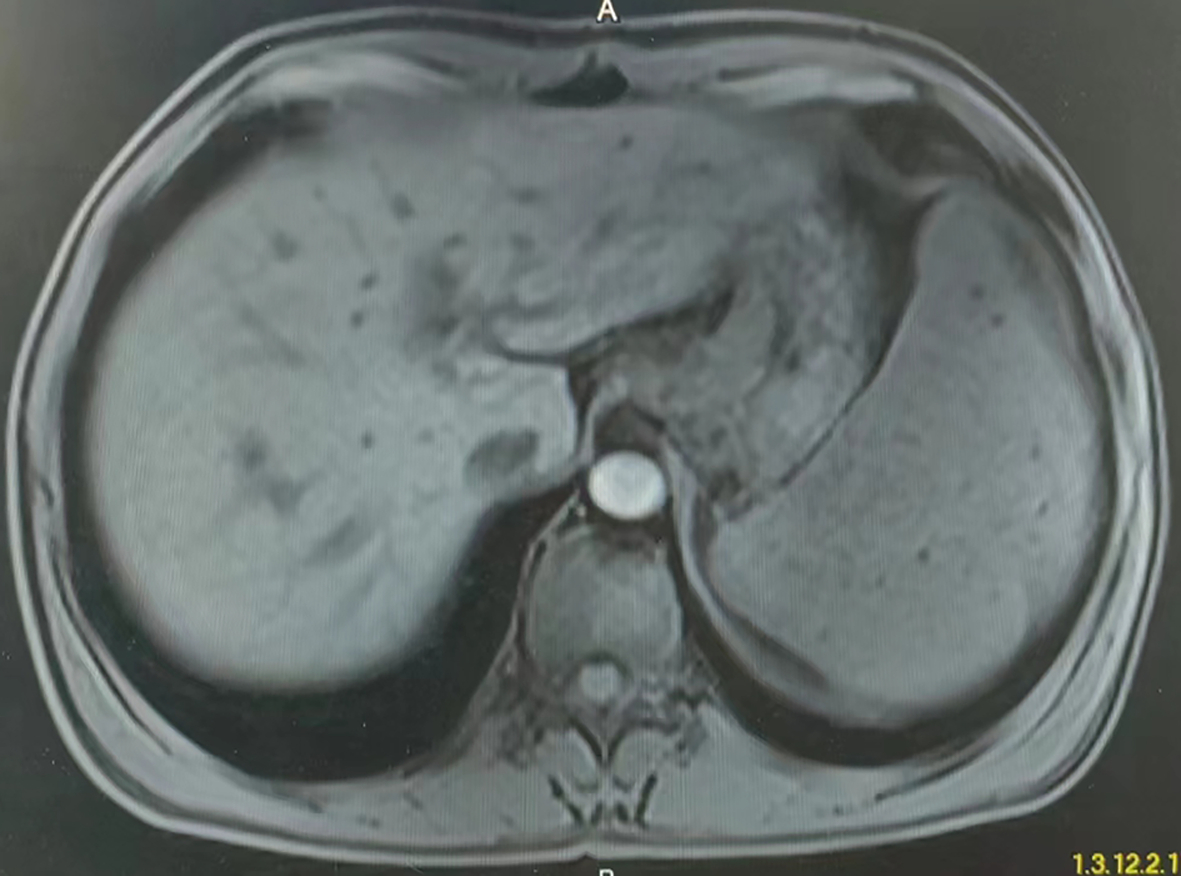

肝窦阻塞综合征成功诊治1例报告

耿雯倩, 朱浩, 杨鑫, 李婉玉, 许芳, 蔡艳俊, 高普均

2023, 39(2): 397-400. DOI: 10.3969/j.issn.1001-5256.2023.02.023

摘要(1455) HTML (476) PDF (2418KB)(134)

摘要: